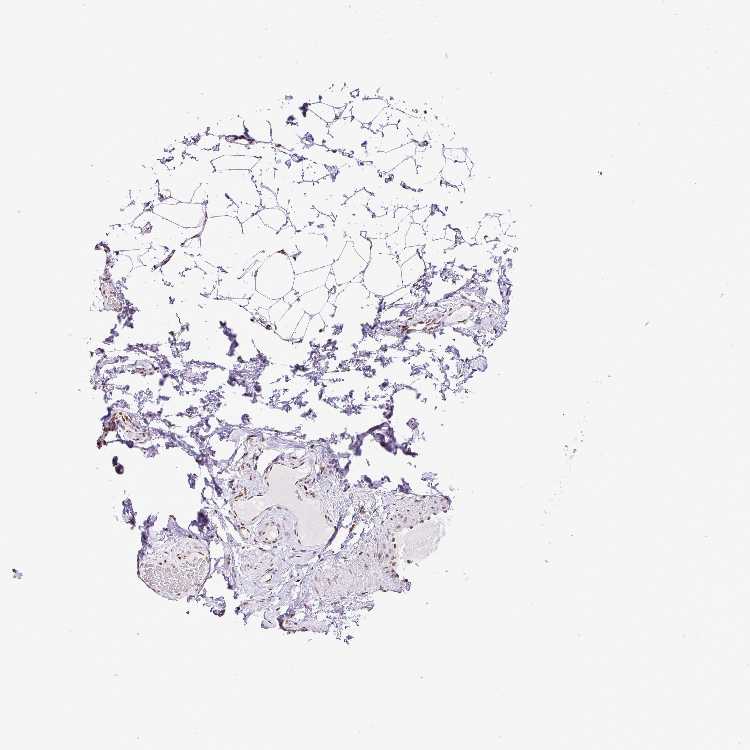

SOFT TISSUE 1 - Antibody stainingi

Antibody staining in the annotated cell types in the current human tissue is reported as not detected, low, medium, or high, based on conventional immunohistochemistry profiling in selected tissues. This score is based on the combination of the staining intensity and fraction of stained cells.

Each image is clickable and will lead to virtual microscopy that enables deeper exploration of all samples and also displays staining intensity scores, fraction scores and subcellular localization as well as patient and tissue information for each sample.

Antibody HPA053883

Chondrocytes Low

Fibroblasts Medium

Peripheral nerve Medium

SOFT TISSUE 2 - Antibody stainingi

Fibroblasts Low